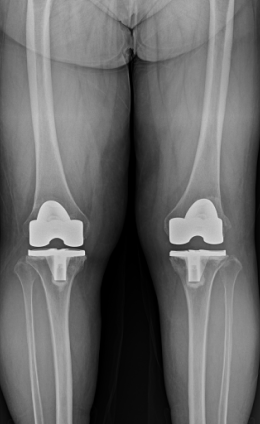

수술 전후 사례

-

수술 후